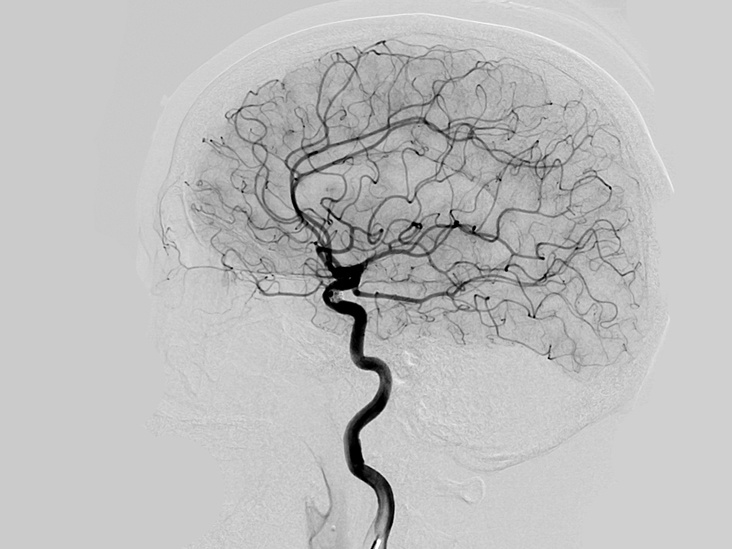

脑血管造影术(DSA):是目前最准确的脑血管检查方法,分辨率最高,是诊断脑血管疾病的“金标准”。缺点是需要进行动脉插管,有微小创伤。在临床实践中,如果通过彩超、MRA或CTA检查,考虑有脑血管疾病的情况,特别是需要进一步介入治疗的时候,需要通过DSA检查最后明确诊断。